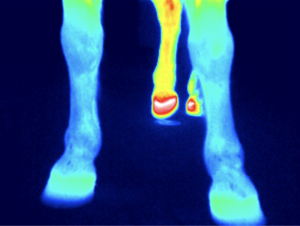

Pferdethermografie

Die Thermografie ist ein bildgebendes Verfahren bei dem entzündete, gereizte aber auch unterversorgte Bereiche aufgedeckt werden können.

Verspannung, Entzündung und Unterversorgung der oberflächlichen Muskulatur kann aussagekräftig dargestellt werden.

Verletzungen, Narben und deren Auswirkungen können sichtbar dargestellt werden.

Ebenso können Zahnprobleme, Hufprobleme oder Blockaden im Pferderücken aufgespürt werden.